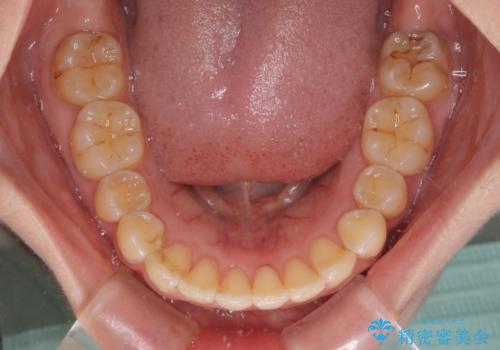

前歯のデコボコを解消 インビザラインによる矯正治療

- 上下前歯のデコボコと深い咬み合わせを気にして来院された患者様です。

インビザラインによる上下歯列の拡大と、IPR(歯と歯の間を削る)にるスペースの獲得により、前歯のデコボコを改善することとしました。

上の前歯をもう少し整えたかったのですが、患者様の治療を早く終了させたいという希望により、細かい叢生を残しての終了となりました。